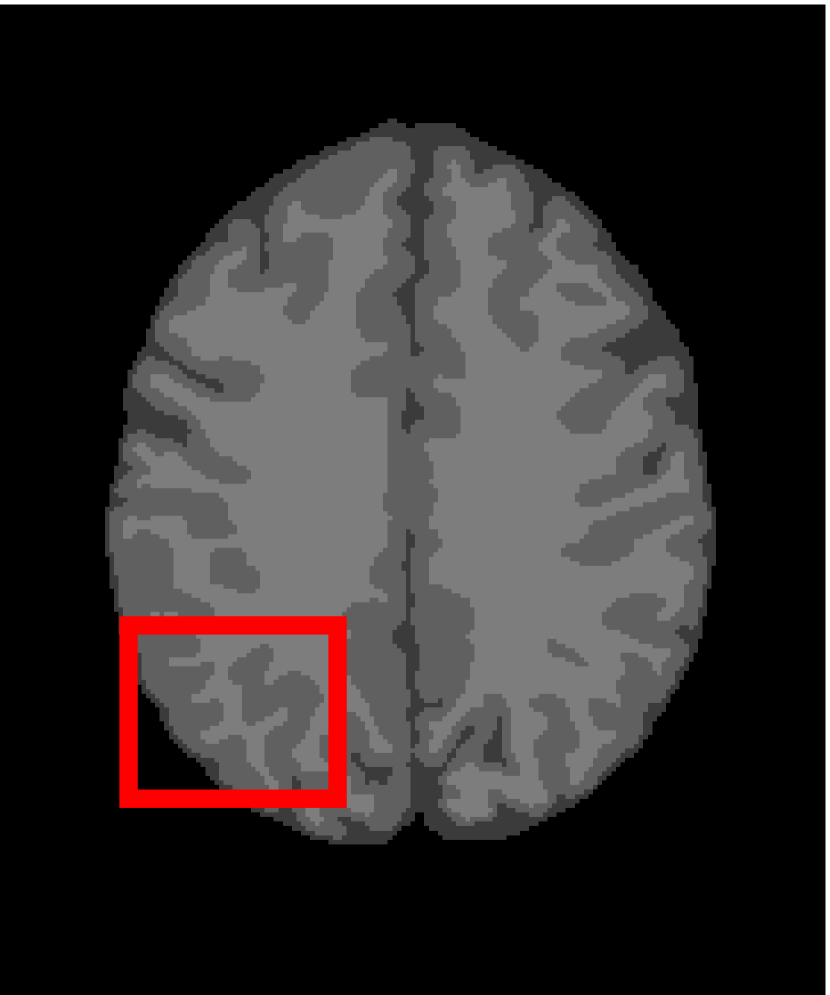

In the second experiments, we segment two medical images coming from a simulated brain database (BrianWeb): http://www.bic.mni.mcgill.ca/brainweb/. The two images are generated by T1 modality with slice thickness of 1mm resolution, 9% noise and 20% intensity non-uniformity. Here, the two images are represented two slices in the axial plane with the sequence of 100 and 110. Moreover, there are golden standard segmentations in the dataset. We set the numbers of clusters to 4. The visual comparisons are illustrated in Figs. 6 and 7.

Figure 7: Segmentation results for the second medical image. From (a) to (l): ground truth, noisy image and results of FCM_S1, FCM_S2, FGFCM, FLICM, KWFLICM, ARKFCM, FRFCM, WFCM, DSFCM_N, and LRFCM.

By focusing on the marked red square in Figs. 6 and 7, we easily find that FCM_S1, FCM_S2, FGFCM and ARKFCM are sensitive to noise. FLICM and KWFLICM are vulnerable to severe intensity inhomogeneity. FRFCM brings overly smooth results due to the use of gray level histograms. WFCM and DSFCM_N cause several contours to change. However, LRFCM acquires clear contours and suppresses noise adequately. Moreover, we find that the segmentation result of LRFCM is closer to ground truth.